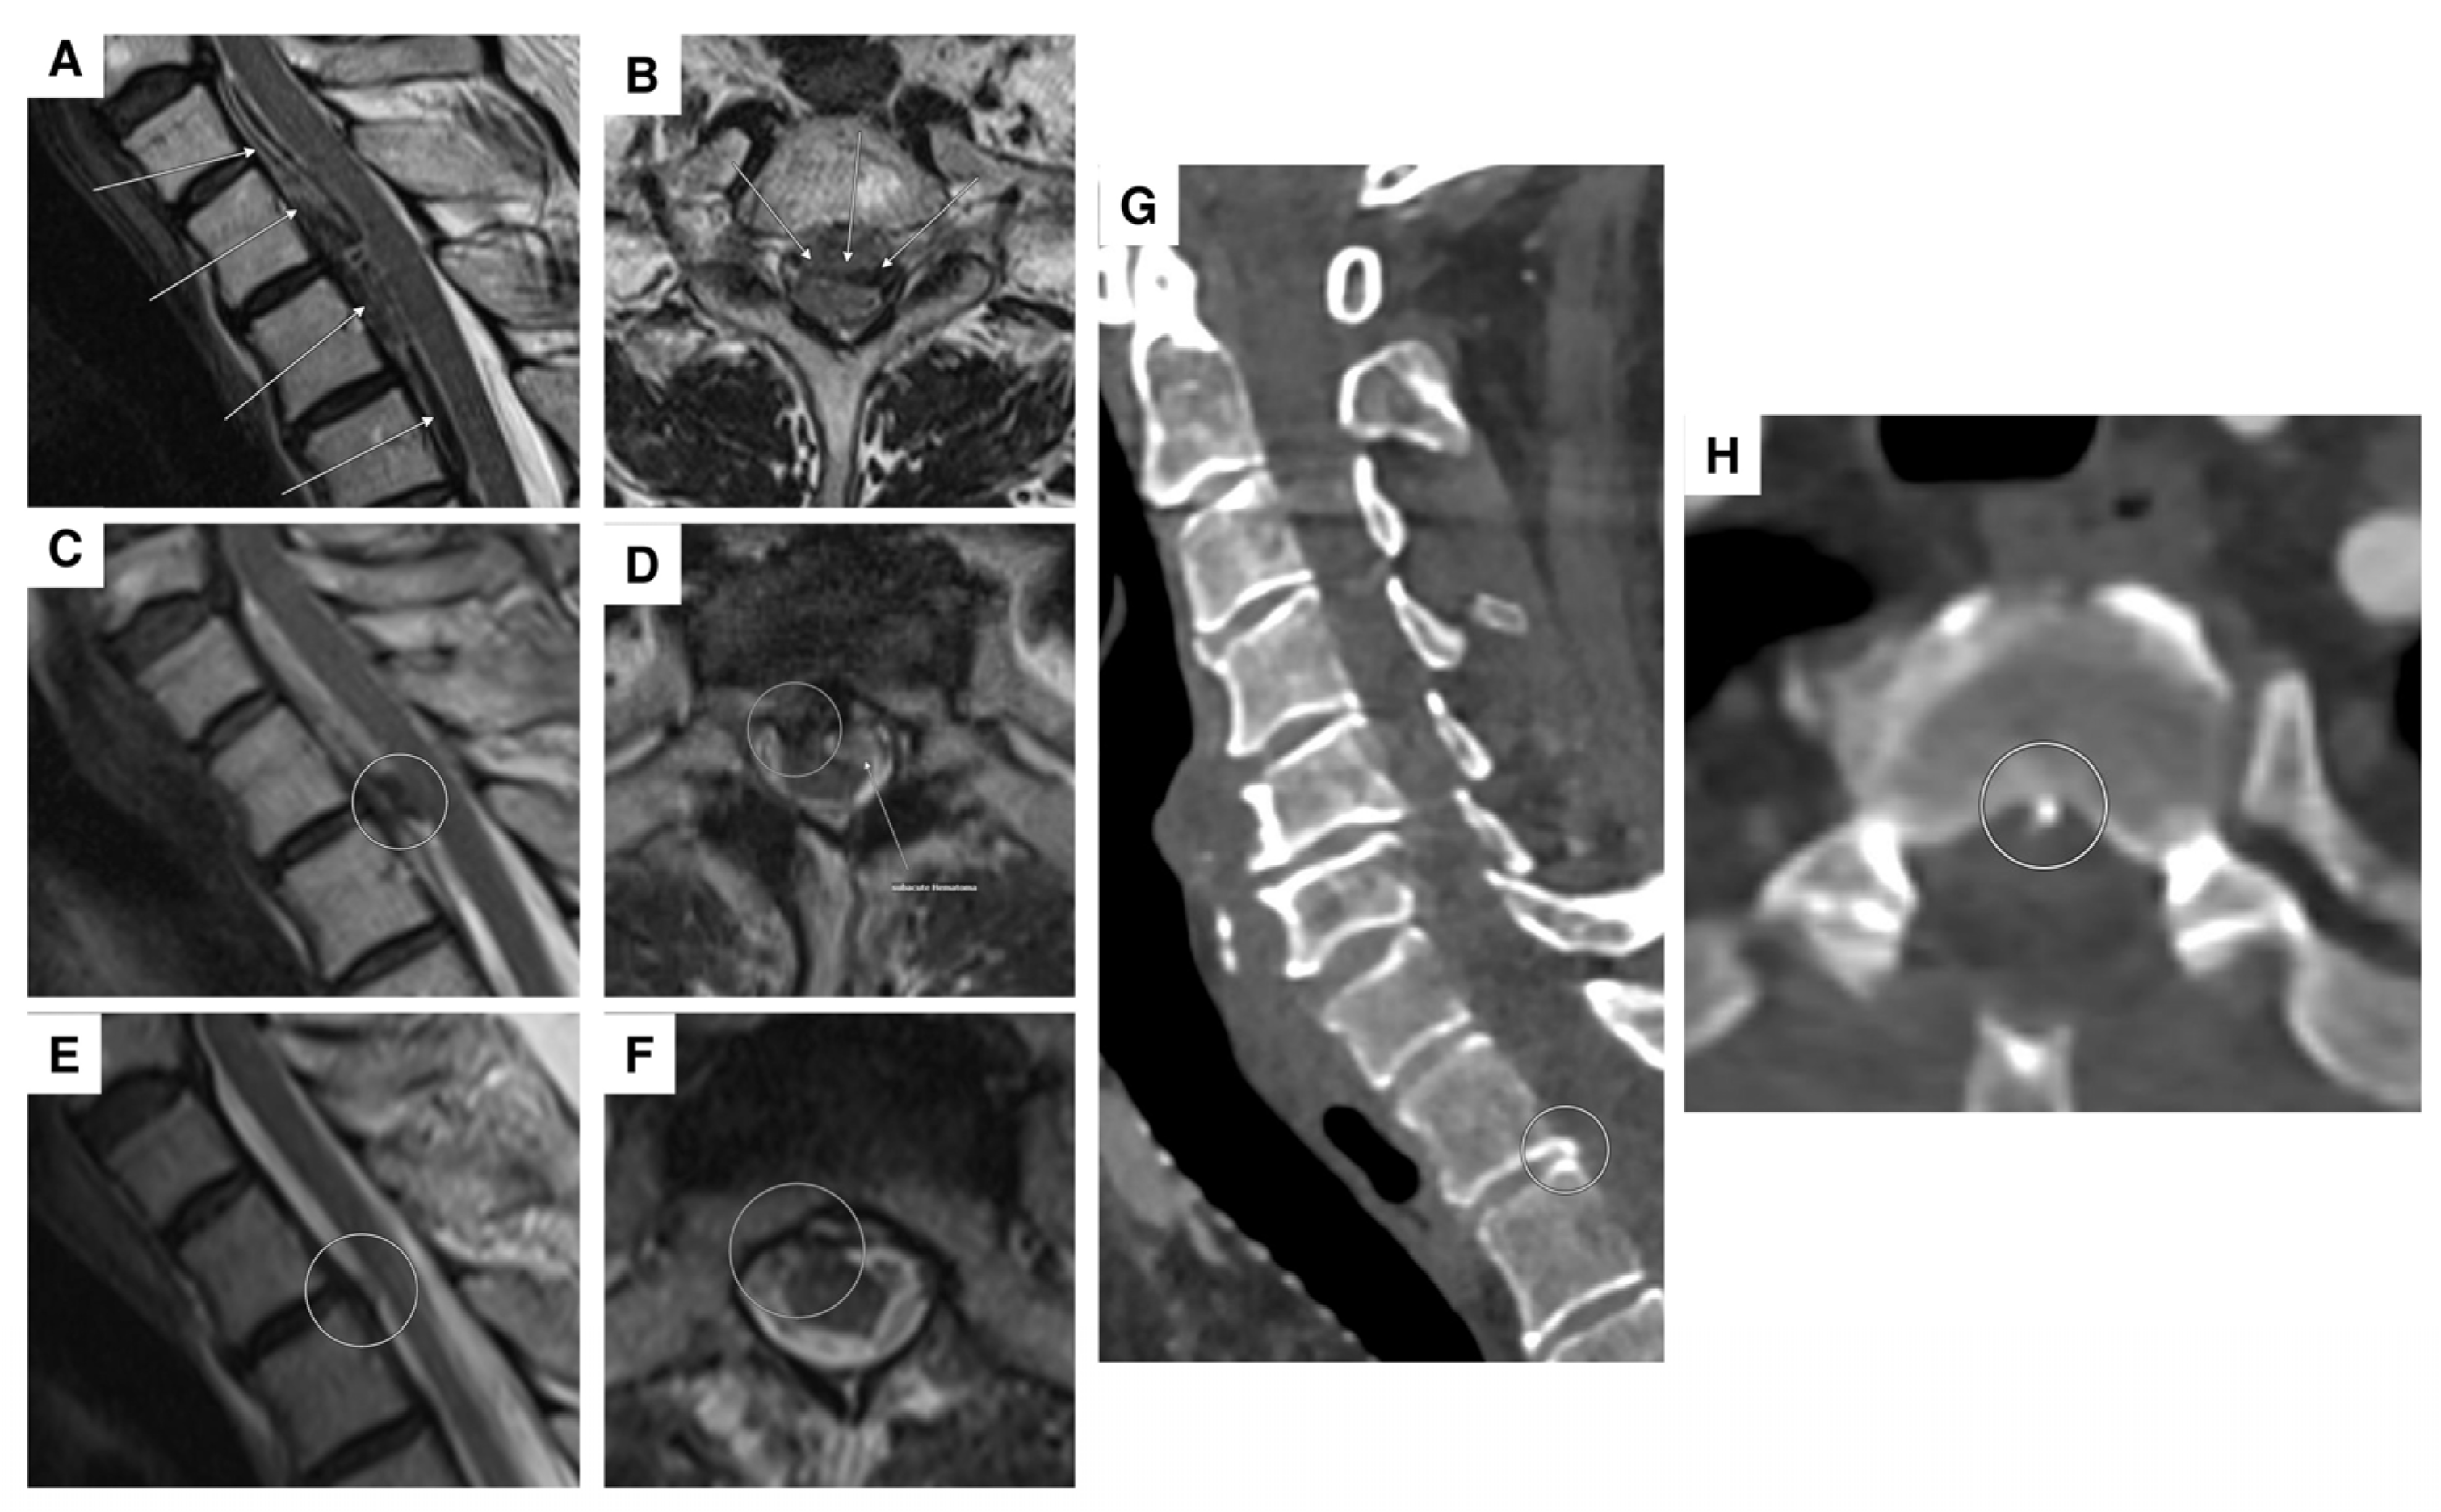

| 1 | F | 47 | headaches and pain in the back/neck pain, nausea, vomiting, photophobia/phonophobia | no focal neurological deficit | SAH Fisher IV with spinal aneurysm at T1 | aneurysm | lumbar puncture, multiple DSA, multiple spinal MRI | conservative |

| 2 | F | 69 | headaches and abdominal complaints | oriented 3×, marked meningism, positive Lasègue sign | spinal SAH with (partial) thrombosed intraspinal aneurysm at T2 | aneurysm | multiple DSA, multiple spinal MRI | surgical procedure (resection of the aneurysm) |

| 3 | F | 25 | acute headaches, complete tetraplegia, bradypnea, and asystole → cardiopulmonary resuscitation with ROSC | hypoesthesia on the left side at C6 and left thoracic and abdominal areas, left hemiparesis, tremor, and hemiataxia | spinal intramedullary aneurysm at C2 with perimedullary fistula | aneurysm | multiple DSA, multiple spinal MRI | surgical procedure (arterial feeder coagulation) |

| 4 | F | 86 | iliosacral pain, paraparesis of the legs, and hypoesthesia from T11 | no evidence of manifest paralysis, intact sensation, unavailable reflexes in the lower extremities | spinal SAH; initially suspected T11 aneurysm; angiographically, no evidence of an aneurysm (spot sign) | anticoagulation (apixaban) | 2 lumbar punctures, repeated abdominal/thoracic CTA, DSA | conservative |

| 5 | F | 73 | headaches and pain in the back/neck pain | pronounced paraparesis of both legs | spinal SAH; angiographically, no evidence of an aneurysm | anticoagulation (rivaroxaban) | abdominal/thoracic CTA, multiple DSA, multiple spinal MRI | surgical procedure (evacuation of an intradural hematoma) |

| 6 | M | 55 | pain between the shoulder blades and the cervical spine, tingling sensations in all four extremities | tingling sensations in all extremities, unable to lift the legs, weakness in both arms | epidural bleeding and spinal SAH; suspected perimedullary aneurysm at T1/2; angiographically, no evidence of an aneurysm, epidural bleeding may be due to a microspur at T1/2 | microspur | multiple DSA, multiple spinal MRI | surgical procedure (evacuation of an epidural hematoma), then conservative (no evidence of an aneurysm) |